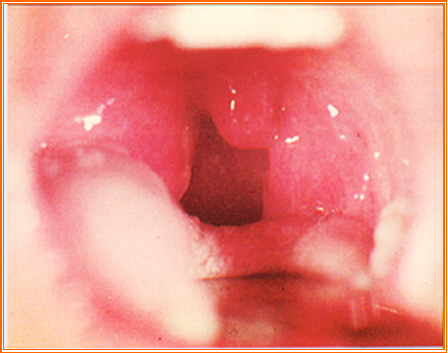

(六)望咽喉

正常咽喉:淡红润泽,呼吸通畅,发音正常,吞咽顺利。

1.咽喉色泽

咽部深红,肿痛明显——实热证;

咽部嫩红,肿痛不显——虚热证;

咽部淡红漫肿——痰湿凝聚。

2.咽喉形态

红肿

喉核红肿,或有脓点——乳蛾(肺胃热盛 / 虚火上炎);

咽痛红肿,身发寒热——喉痈(脏腑蕴热,热毒客咽)。